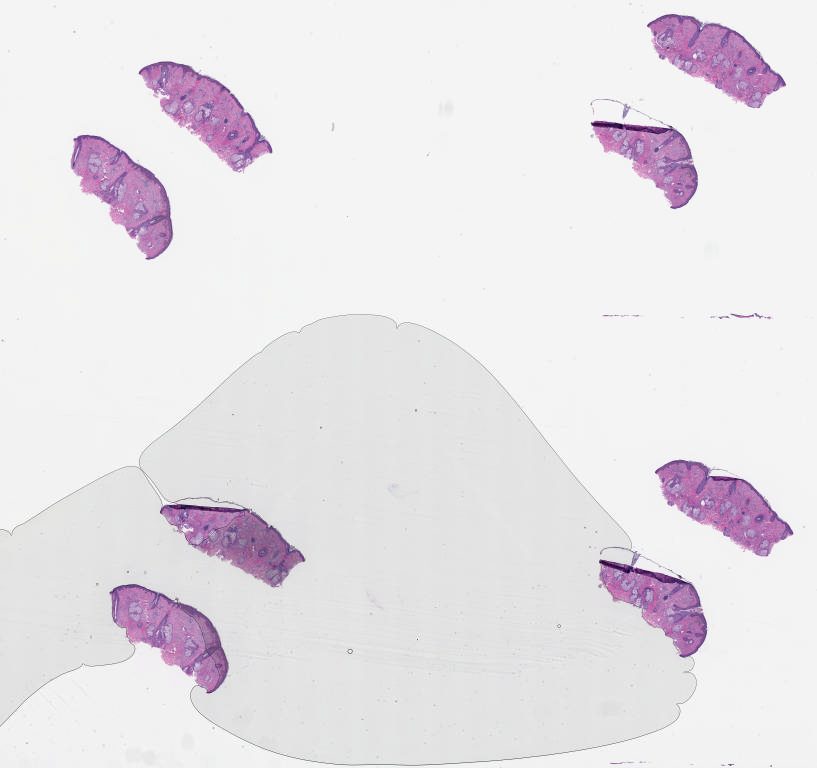

University of Pittsburgh Oral Pathology Study Set Summer 2025\Case13

1730160.svs

20X